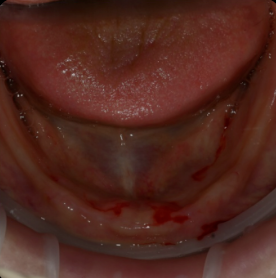

실제 환자분들의 깨끗한 통지르코니아 잇몸 반응